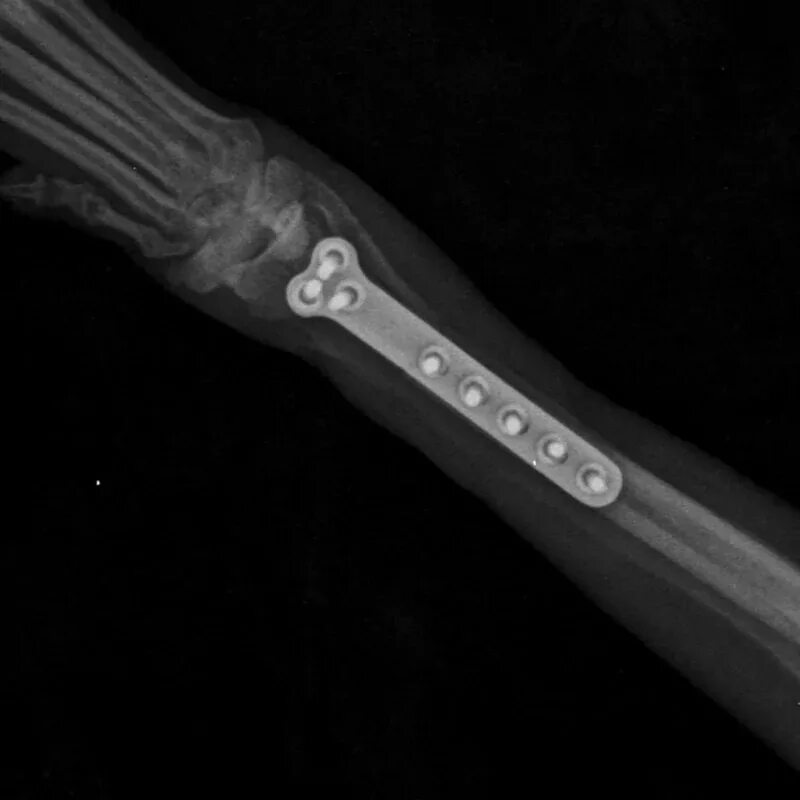

Остеосинтез мрт